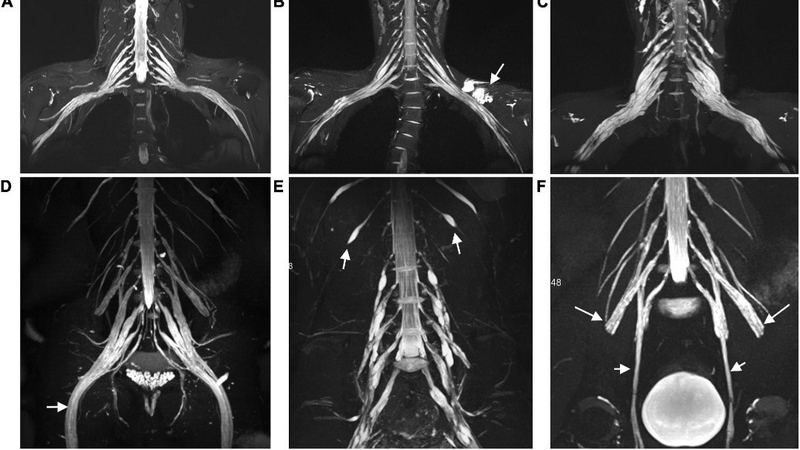

Chụp cộng hưởng từ dây thần kinh ngoại biên (Neurography MR) là một phương pháp chẩn đoán hình ảnh tiên tiến và hiện đại giúp phát hiện các bệnh lý liên quan đến hệ thống dây thần kinh ngoại biên. Kỹ thuật này mang lại nhiều ưu điểm với khả năng phát hiện tổn thương nhỏ, độ chính xác cao, không xâm lấn, không sử dụng tia X, không gây nhiễm xạ và đem lại giá trị chẩn đoán cao.

Hình ảnh thu được từ chụp cộng hưởng từ dây thần kinh ngoại biên có độ chi tiết cao, rõ ràng và tương phản tốt, mang lại giá trị lớn trong quá trình chẩn đoán. Ngoài ra, phương pháp này cho phép quan sát từ nhiều góc độ khác nhau mà không yêu cầu thay đổi tư thế của người chụp.

Kĩ thuật chụp MRI dây thần kinh ngoại biên giúp phát hiện các tổn thương liên quan đến dây thần kinh ngoại biên. Với khả năng phát hiện những thay đổi nhỏ trong cấu trúc, phương pháp này mang lại độ chính xác và độ nhạy cao trong việc chẩn đoán và theo dõi quá trình điều trị bệnh.